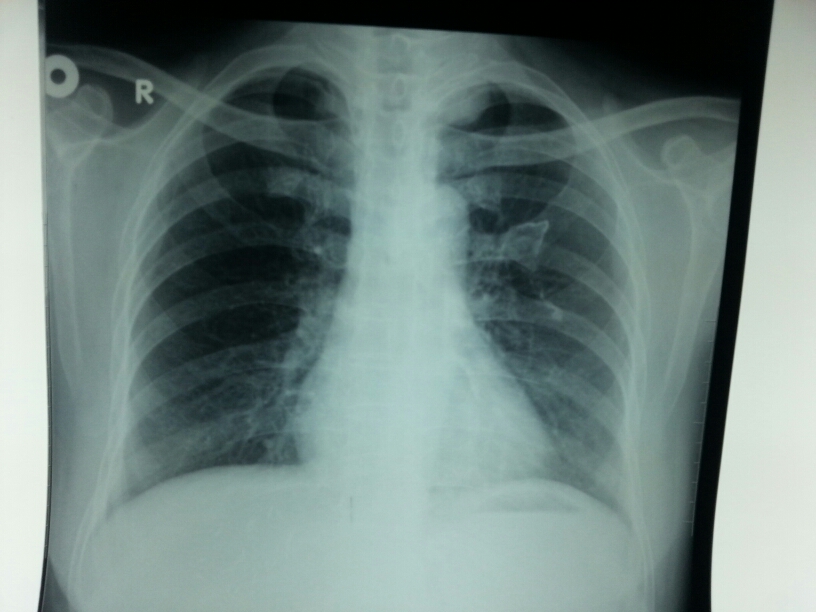

X13674:左肺病灶大家帮看下!

左肺尖纵隔旁结节灶,边缘光滑。神经源性肿瘤?肺部肿瘤?建议CT检查。

考虑左侧第二肋软骨钙化

考虑纵膈占位性病变,神经源性肿瘤?建议进一步检查。

软骨钙化,纵膈占位性病变,建议CT检查。

第2肋骨骨软骨瘤

最近几个月遇到几例跟本片几乎一样的片子。最后都是脊神经的肿瘤。侧位片有用,只要是包块靠后就可能性大了。

左侧第二前肋肋软骨钙化,左肺肺尖可见边缘光滑,密度均匀的高密度影